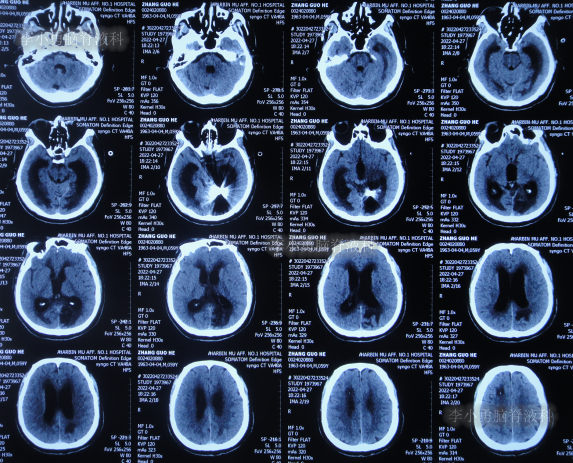

2022年3月23日(脑动脉瘤栓塞术后5天),查头颅CT示积血减少(图-3);术后身体恢复良好,能自行下地活动。

图-3:2022年3月23日头颅CT

但出院回家后半个月即2022年4月18日,再次出现嗜睡,言语有时混乱,有走路不稳的症状,持续1周并没有好转反而逐渐加重,于是2022年4月25日(出院后22天),第2次返回给予手术的医院,查头颅核磁增强示脑积水(图-4);给予腰椎穿刺治疗。

图-4:2022年4月25日头颅核磁增强

2022年4月27日(入院治疗3天),脑脊液培养出细菌,给予抗感染治疗,查头颅CT示脑室扩张加重(图-5)。

图-5:2022年4月27日头颅CT